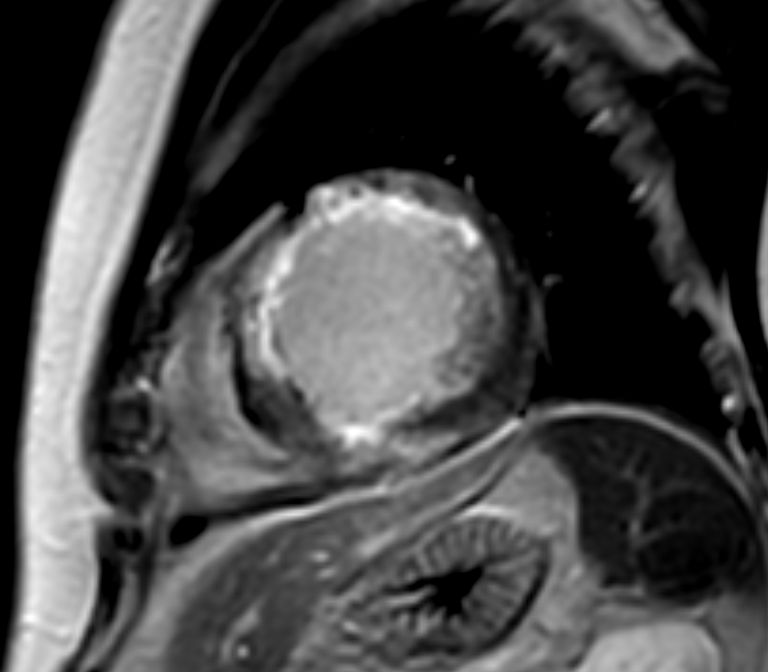

Short axis view cine

Short axis view T2w Black Blood

Short axis view T1 Map (native)